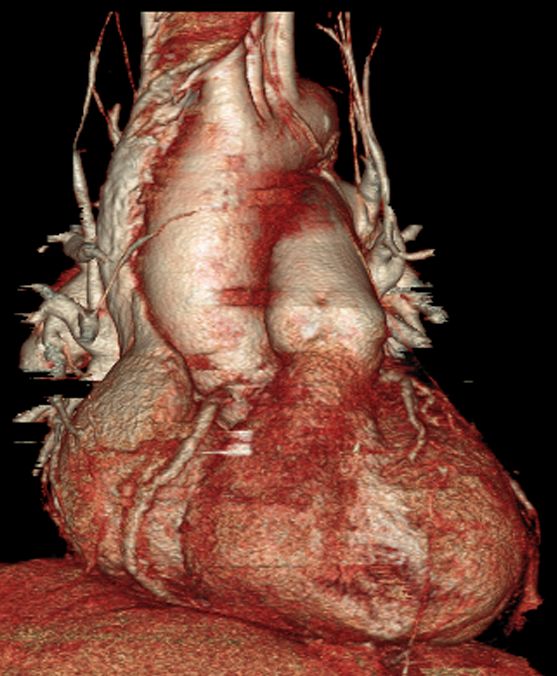

Domande su Aneurisma aortico

Buongiorno,

mio babbo in seguito ad aneurisma all'aorta ha subito un intervento dove gli hanno installato una protesi nel torace nella curva ascendente dell'aorta.

I medici hanno ipotizzato che la protesi impiantata lo scorso anno all'aorta si sia allargata o mossa e che tocchi dei nervi di bocca, gola e epiglottide e che causi questi disturbi.

chiedo io: e' possibile che una protesi artificiale all'aorta si sposti o si allarghi??? A ME SEMBRA UNA COSA ASSURDA, sto chiedendo parere anche a voi

se ho capito bene la protesi è stata impiantata 1 anno fa?! è impossibile che si sposti, fa parte integrante dell'aorta, .

E' invece possibile che vi sia un ulteriore dilatazione a monte o a valle della protesi.

Dr. Guidalberto Guidi